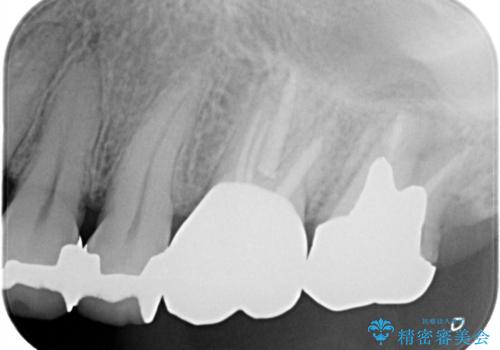

【根管治療】未処置根管を有した歯の再根管治療

- 定期検診にて虫歯を見つけたため、根管治療からオールセラミッククラウンによる修復治療を行いました。

レントゲンにて透過像を認めている上顎第二大臼歯も治療予定です。

上顎第一大臼歯の近心根にはほとんどの場合、神経の管が二本あることが多いです。顕微鏡を用いることで見逃すことなく治療が行えました。